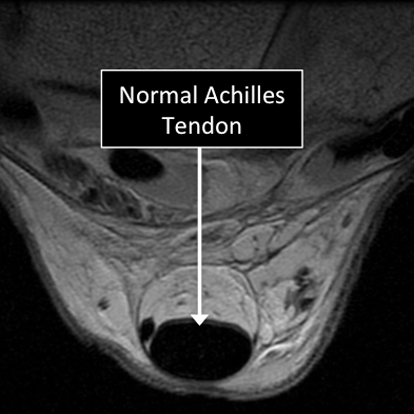

MRI allows us to see the structure of the tendon.

Several injuries or diseases affecting the tendon can be diagnosed using MRI.

Common things affecting the tendons include degenerative or traumatic tears, abnormal calcium deposition in the tendons or adjacent to them, tendon degeneration, ganglion cysts (abnormal collections of fluid) in or adjacent to tendons, among others.

Ankle MRI examinations showing normal (top) and abnormal (bottom) Achilles tendon.

- Tendons are one of the several structures that can’t be seen (they look black or dark) with the standard MRI.

- There are new “software” programs that allow us to see structures with different contrast (bright versus dark).

Ankle MRI examinations using the standard MRI techniques (top) and translational MRI techniques (bottom).